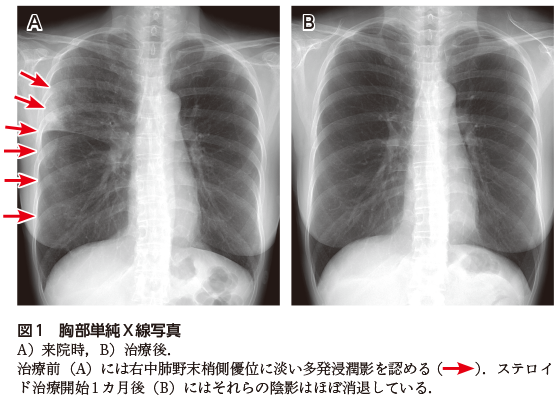

肺炎の画像診断と最新の診療 新型コロナ/富士フイルム、AIで肺炎診断支援 技術開発の詳細情報

新型コロナ/富士フイルム、AIで肺炎診断支援 技術開発。解答・解説】1カ月続く乾性咳嗽を主訴に受診した60歳代女性。肺CT検診 | JR仙台病院。肺がんの診断、特にCTとPET 豊田 尚之 - YouTube。「肺炎の画像診断と最新の診療」藤田次郎定価: ¥ 12,540#藤田次郎 #本 #BOOK #健康 #医学